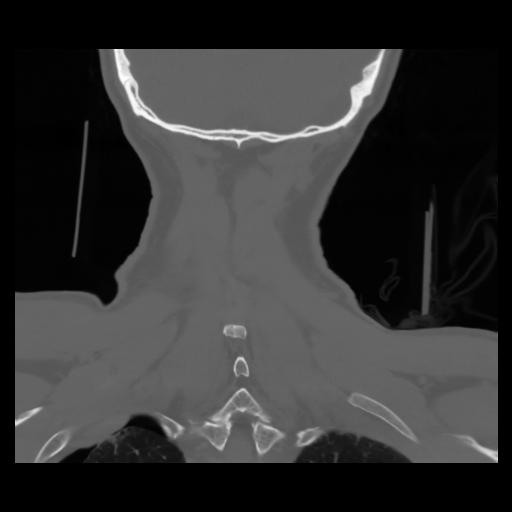

13 P.BLANDAS,,Coronal,2.000,P.BLANDAS,Coronal,